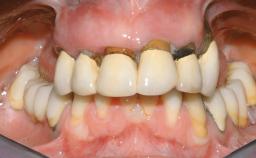

Immediate Loading of Six Implants in the Maxilla and Final Restoration with a Full-Arch CAD/CAM Zirconia FDP

A 63-year-old male patient was referred for a consultation and treatment of partial edentulism in the maxilla. The patient presented with residual anterior teeth and declined a partial removable prosthesis. He reported that the maxillary posterior teeth had been extracted due to mobility and periodontal disease two months before the consultation. The patient’s chief complaint was that his residual maxillary teeth were mobile and that he was unable to chew. The patient’s desire was a stable and comfortable fixed maxillary rehabilitation. The patient was a light smoker (fewer than 10 cigarettes/ day), and his medical history was without significant findings. He was not on any regular medication at the time of consultation. The extraoral examination revealed a normal physiognomy with a correct distribution of the facial thirds. The patient presented a low lip line, and the transition line between teeth and soft tissues was not exposed during a forced smile.

Prosthesis Type FDP

Loading Protocol Immediate

Occlusal Scheme/Issues Anterior guidance